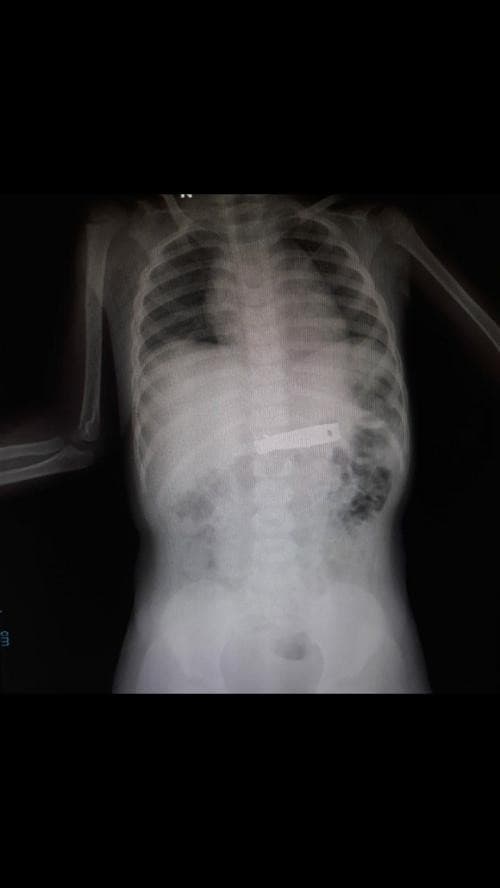

Pasien mungkin memerlukan rontgen pada leher, toraks (dada), sakrum atau tulang ekor, atau lumbosakral. Tujuan dari rontgen tulang belakang antara lain mengetahui patah di tulang belakang. Selain itu juga berguna melihat ada atau tidaknya dislokasi (pergeseran) pada area tulang belakang.

Rontgen tulang belakang akan membantu dalam menemukan penyakit dan cedera yang mengenai tulang belakang, sendiri, serta diskus-nya (cakram atau bantalan antar tulang). Umumnya, dokter atau petugas radiologi akan melakukan pemeriksaan x-ray tulang belakang untuk mendiagnosis masalah yang berhubungan dengan tulang belakang.